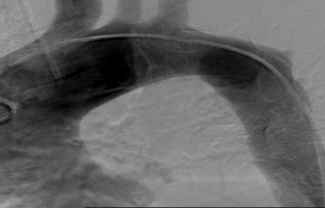

Patient N. Male, 80 years old, underwent a routine examination at the place of residence in November 2019, and where an increase in the contours of the aortic arch was accidentally detected on a chest x-ray. The patient was examined by an angiosurgeon at the place of residence and received recommendations for optimal drug therapy, followed up until 2221. In May 2021, he began to notice the appearance of blood streaks in the sputum when coughing, in connection with which he consulted an angiosurgeon, who sent him for CT angiography with contrast. (Fig.1.)

Figure. 1 Aneurysm of the descending aorta with wall dissection, type IIIb according to DeBakey.